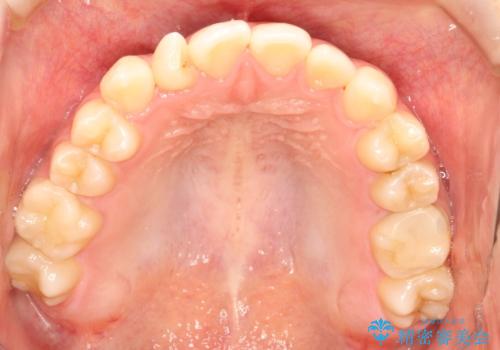

- 前歯の捻れを主訴に来院されました。

インビザラインを希望されておりましたが、20時間もつけることができなかったためワイヤー矯正にて叢生の改善を行っています。

右上の側切歯(前から2番目の歯)が90度程度ねじれている状態でしたが、1月に1回のワイヤー交換できれいに並ぶことができ満足いただけました。

捻れた歯の治療に関しては、ワイヤー矯正の方が仕上がりがきれいに治りやすいです。